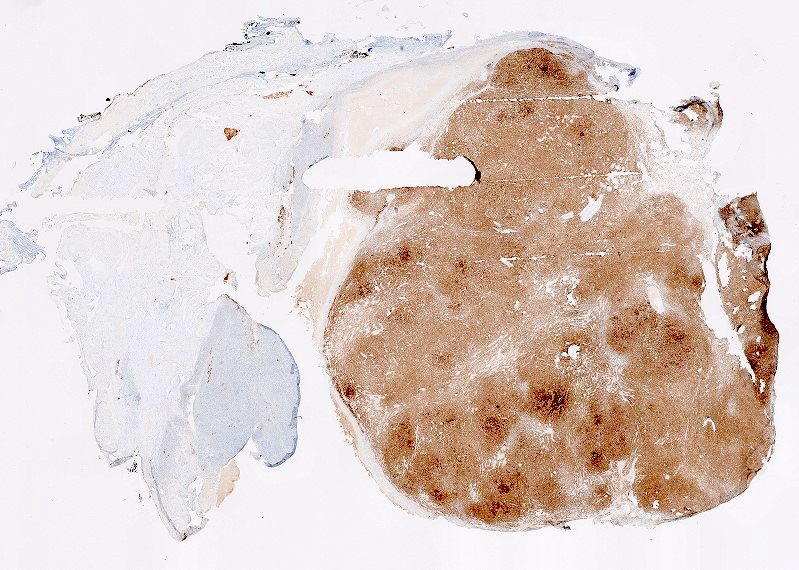

Gross description

- Usually unilateral

- Most are < 5 cm

- Solid, yellow and lobulated or white with focal yellow areas

- Occasionally cystic change and hemorrhage are present

- Necrosis is rare (Am J Surg Pathol 2014;38:1023)

Gross images